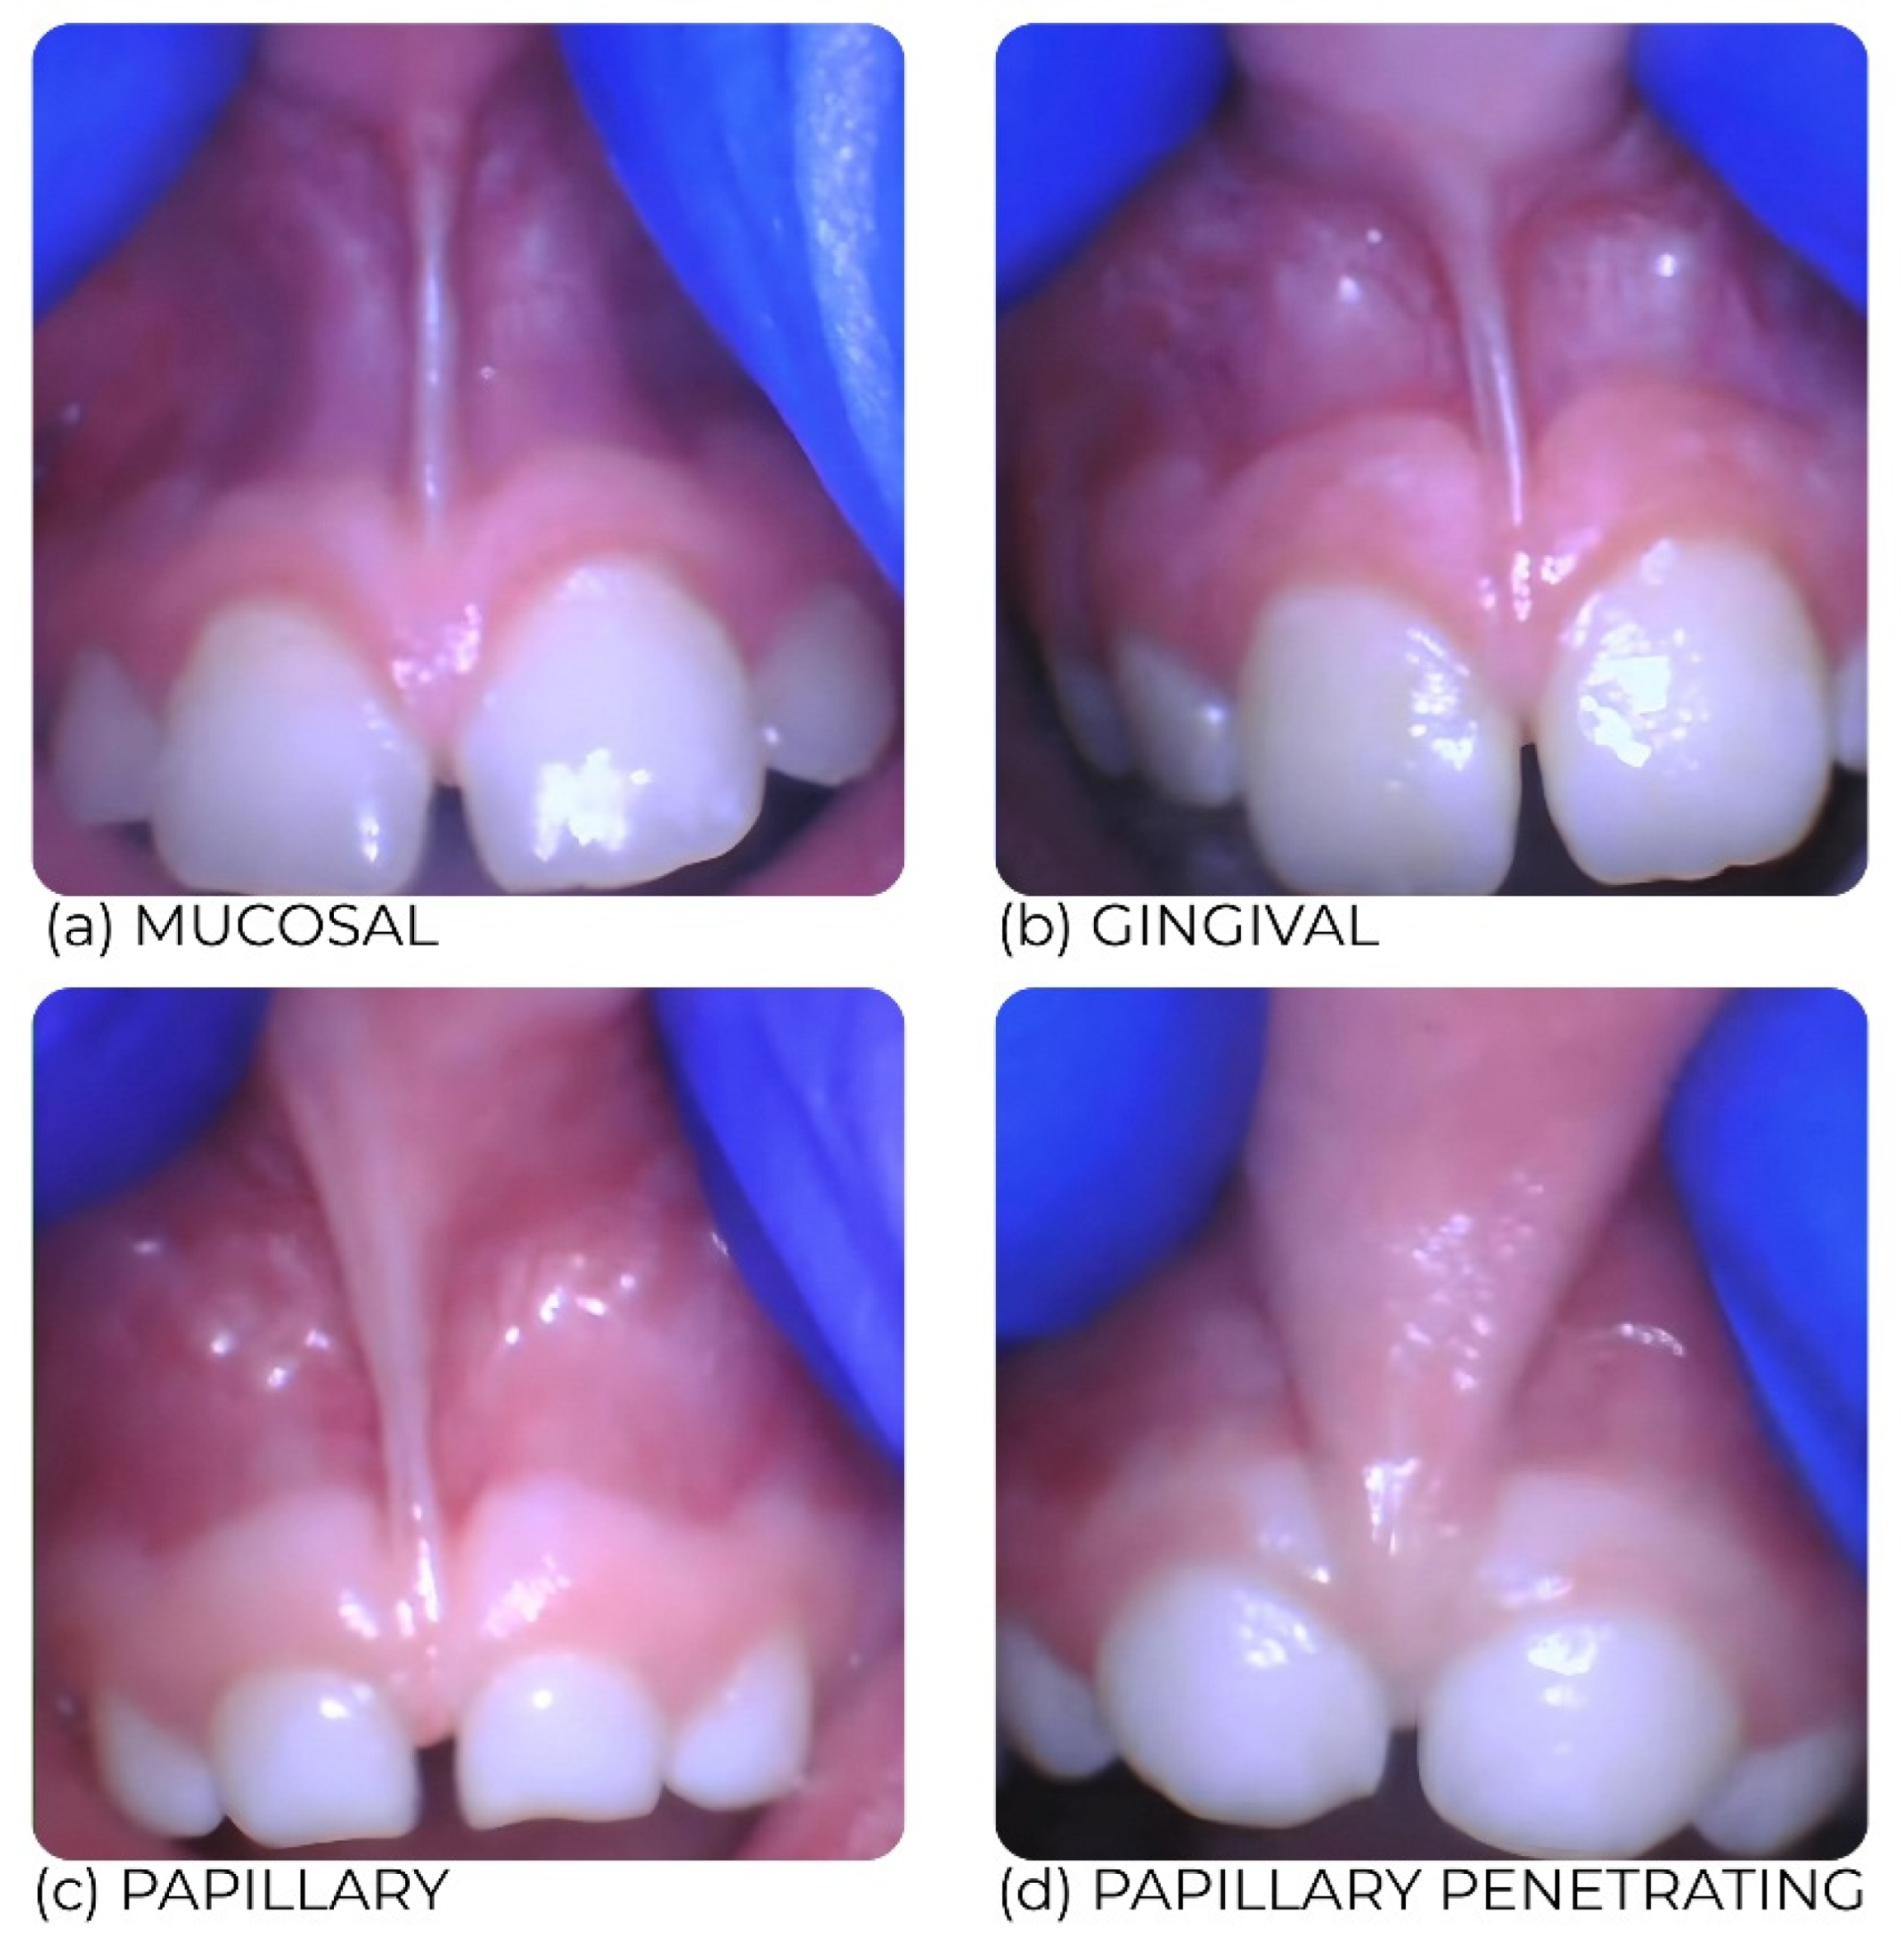

- Frenum morphology (primary exposure): classified as mucosal, gingival, papillary, or papillary-penetrating.